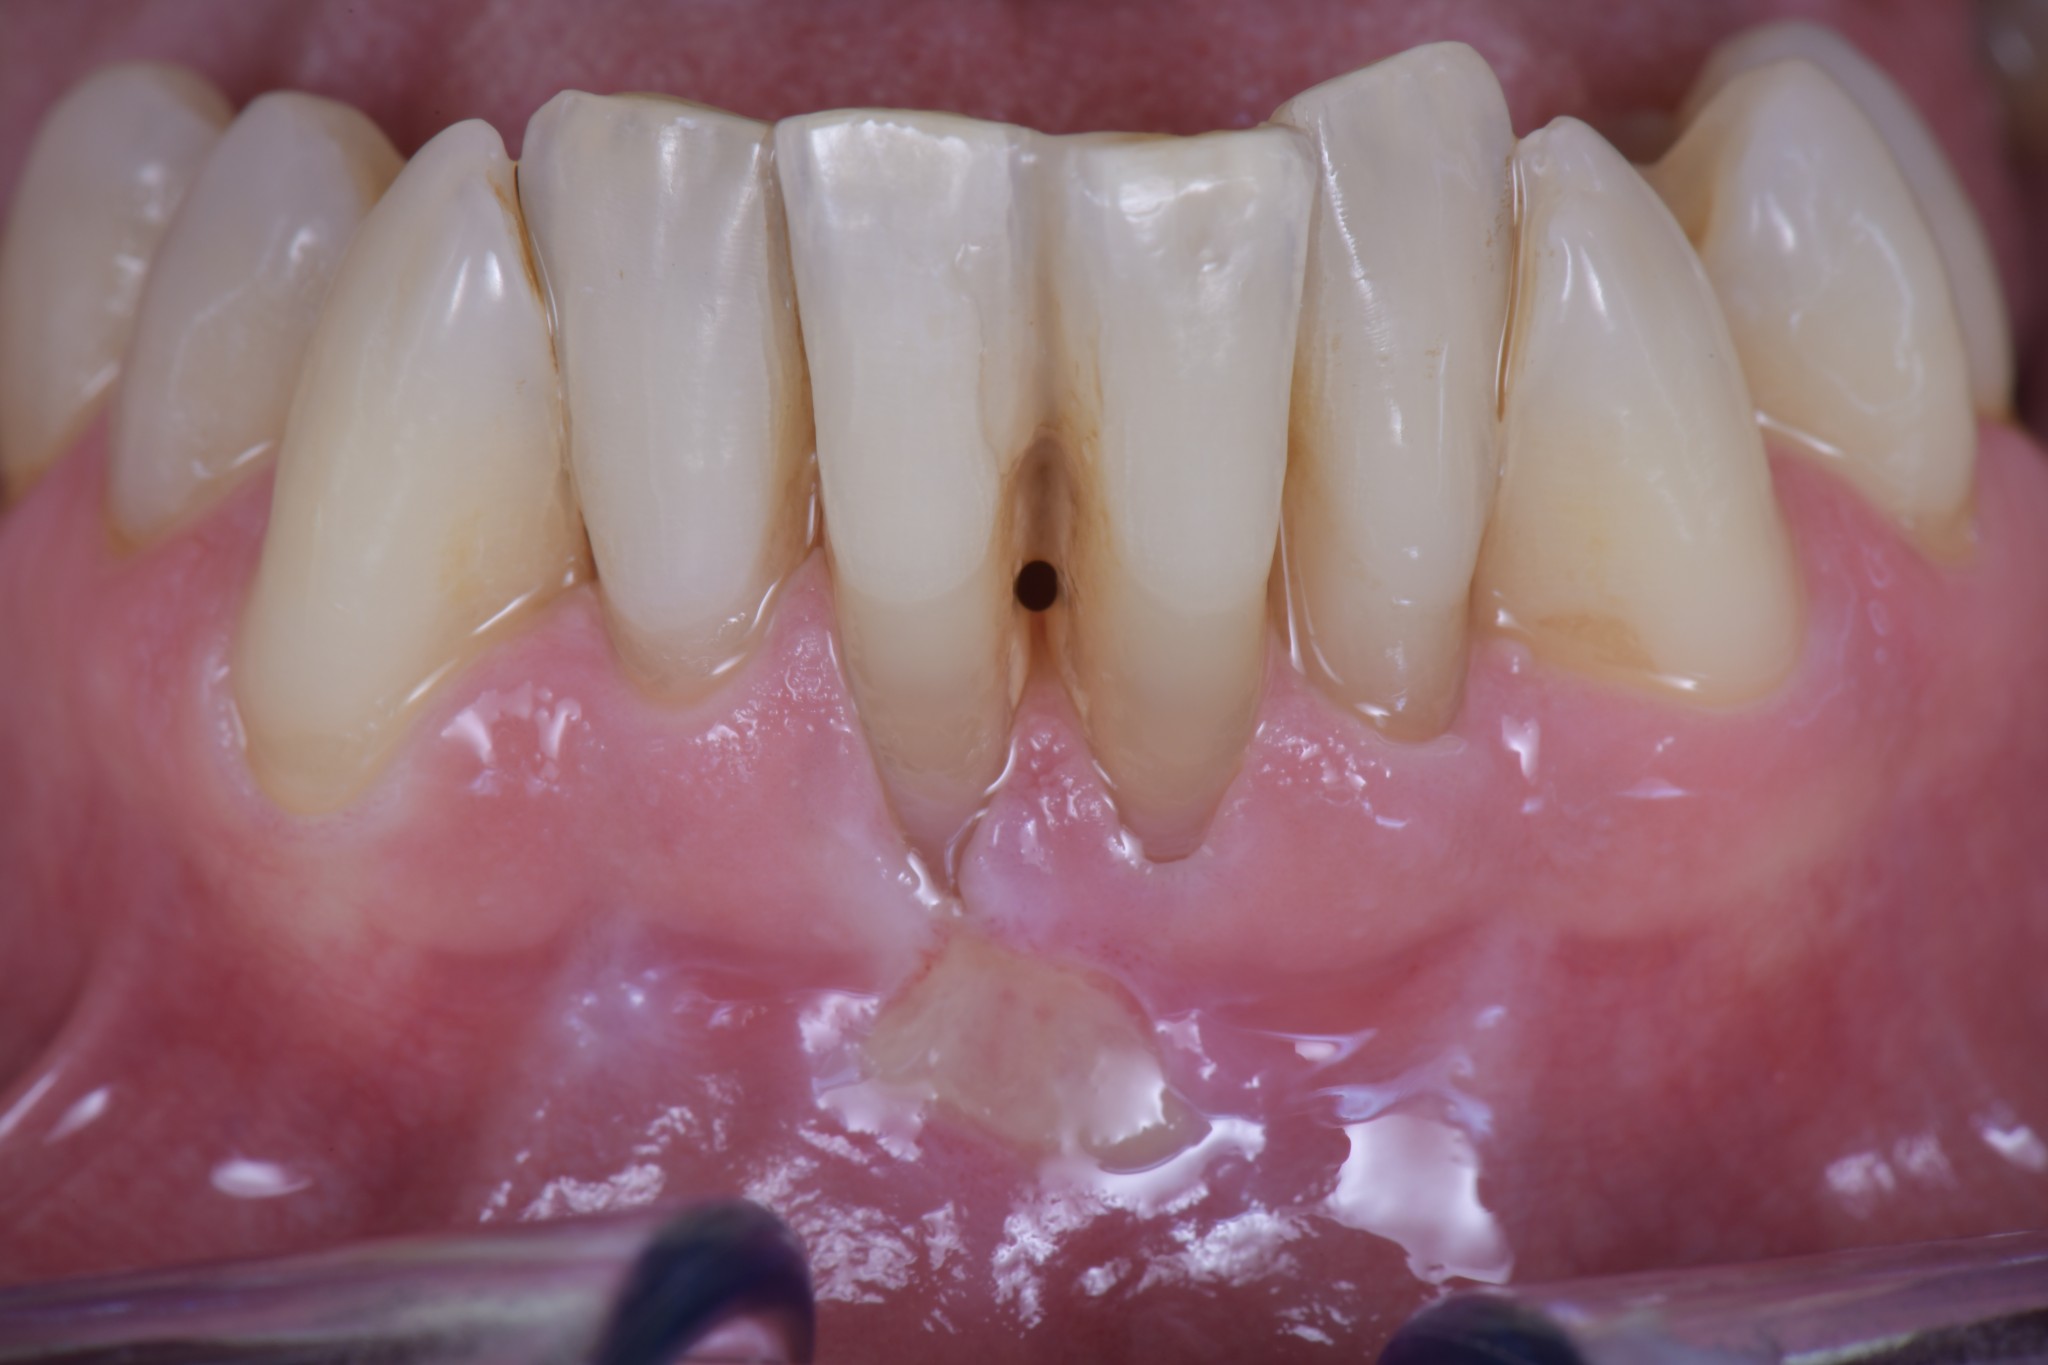

Il mio paziente si era presentato in visita con una ferita ricorrente da spazzolamento facilitata dalla scarsa qualità dei tessuti e dalla completa assenza di tessuto cheratinizzato.

In un caso del genere, vista la grave perdita di attacco, una ricopertura radicolare completa sarebbe ovviamente impossibile ed una ricopertura parziale sarebbe difficilmente predicibile nel risultato. Dopo la terapia causale e le istruzioni d’igiene con conseguente risoluzione della lesione, ho allora deciso di limitarmi a creare una banda di tessuto cheratinizzato che consentisse al paziente di spazzolare sereno…